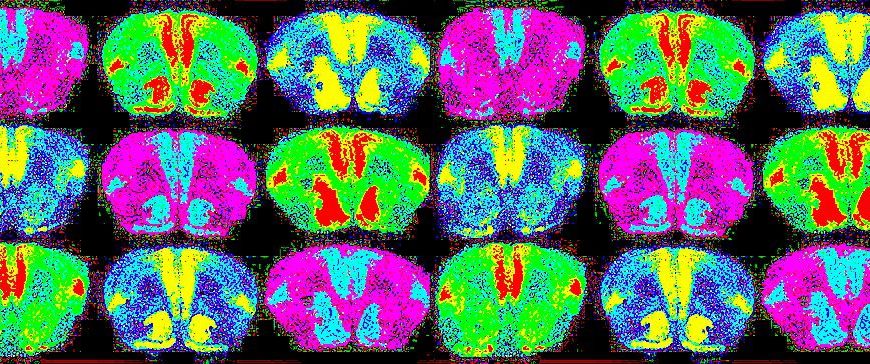

Мозъчните клетките не бързат да се възстановят, хората бързат. Доктор Джил Болти Тейлър е невроанатoм, възпитаник на Харвард, който дълги години се занимава с изследване на мозъчната функционалност и преподавателска дейност. На 10 декември 1996г., 37-годишната д-р Тейлър претърпява рядка форма на мозъчен кръвоизлив в лявото полукълбо. В продължение на четири часа тя наблюдава как мозъкът й напълно губи способността си да обработва информация, докато … Continue reading Д-р Джил Болти Тейлър за личното и научното прозрение след прекаран инсулт.